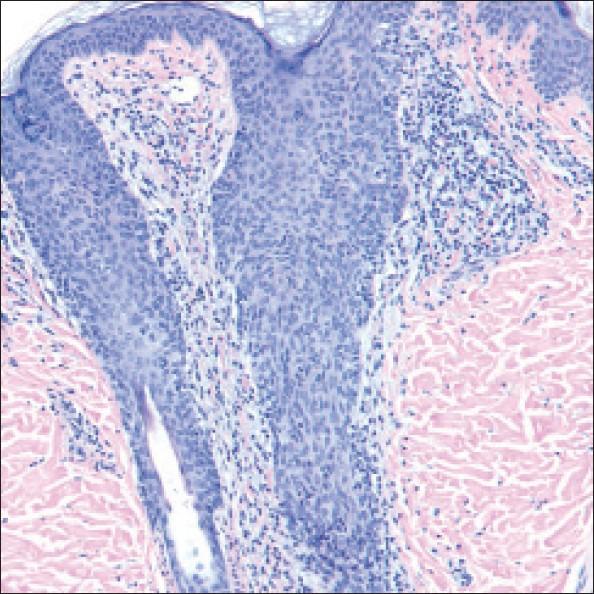

Follicular mucinosis.

Follicular mucinosis is an uncommon inflammatory disorder that characteristically presents as follicular papules and/or indurated plaques. The face, neck, and scalp are the most frequently affected sites, although lesions may occur on any site of the body. Histologically, the disorder is characterized by mucin deposition in the follicular epithelium. The condition is frequently divided into primary and secondary forms, with the latter form frequently associated with mycosis fungoides. In this case report, we describe a child with follicular mucinosis of the back and trunk and discuss the clinical variants, histopathological pattern, and treatment options.